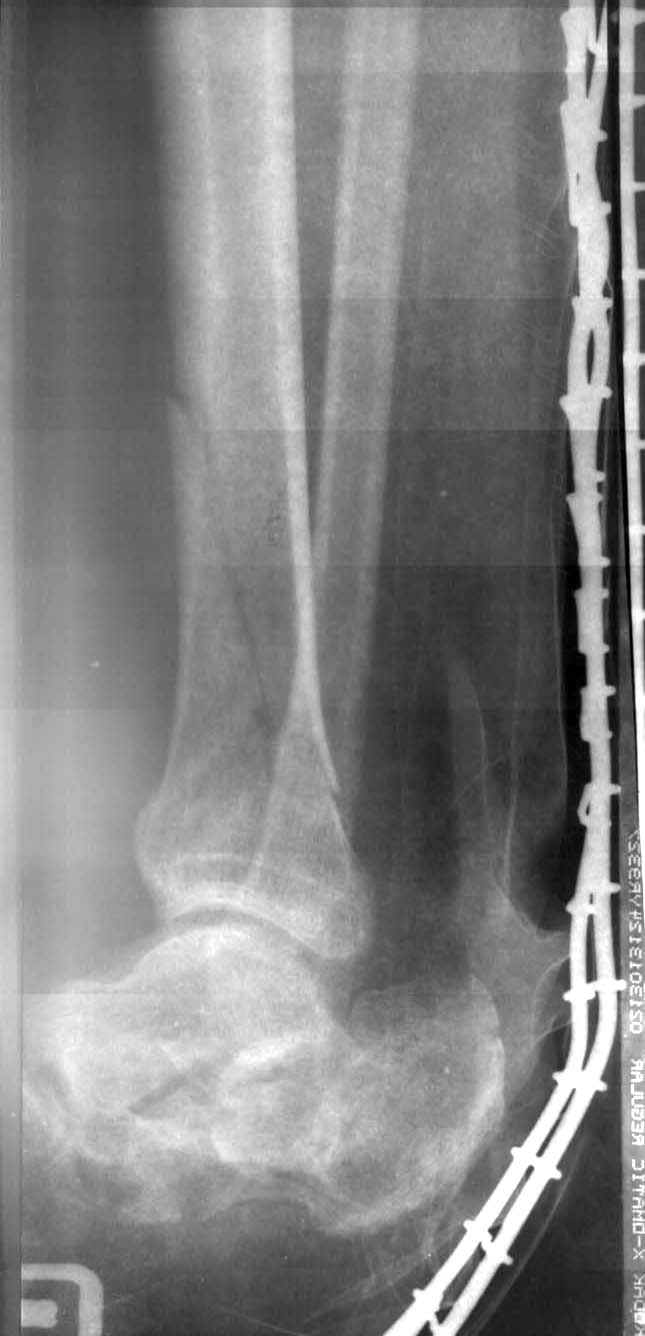

Мужчина, 33 года. Травма при падении с 6 этажа. Диагноз: шизофрения (стадия обострения?), открытый перелом левой голени, закрытый перелом правой голени, открытый перелом правой пяточной кости, ушиб почек, забрюшинная гематома.При поступлении выполнено ПХО, наложены задние гипсовые лонгеты, лапароцентез, противошоковая терапия. Вопрос: дальнейшее лечение (внешняя фиксация противопоказана, стоит ли оперировать или продолжить лечение в гипсовой повязке)? Особенно интересует пяточная кость.

На такой пятке, как у молодого человека ходить можно, лишь хромая.

Для уточнения же тактики травматологической желательны рентгенограммы как минимум в двух проекциях, лучше - КТ. Да и о голенях не надо забывать.

Открытый перелом пяточной кости - это абсолютное противопоказание к оператиному лечению в ранние сроки, не зависимо от того, что вы хотите выбрать открытую репозицию, остеосинтез или закрытую и АНФ.

А в более поздние сроки, когда заживут раны, субэпидермальные пузыри (не менее 3 нед) закрытая репозиция и АНФ врядли оправдают надежды (если только как плацебо), а открытая репозиция, остеосинтез возможны.

Но как показывают наши наблюдения, при открытых переломах пяточной кости нужно стремитьтся на первом этапе не к репозиции, а к скорейшему заживлению раны.

При лечении шизофрении+политравмы, мое мнение, метод выбора при О. переломе пяточной кости при поступлении ПХО без зашивания раны, гипс с окном и постараться устранить валгусное или варусное смещение пятки, после заживления раны продолжить конс лечение желательно в ПНД.

Если больного в последующем будет беспокоить

пятка вернуться к вопросу об оперативном лечении через 6 мес и после купирования обострения основного заболевания.